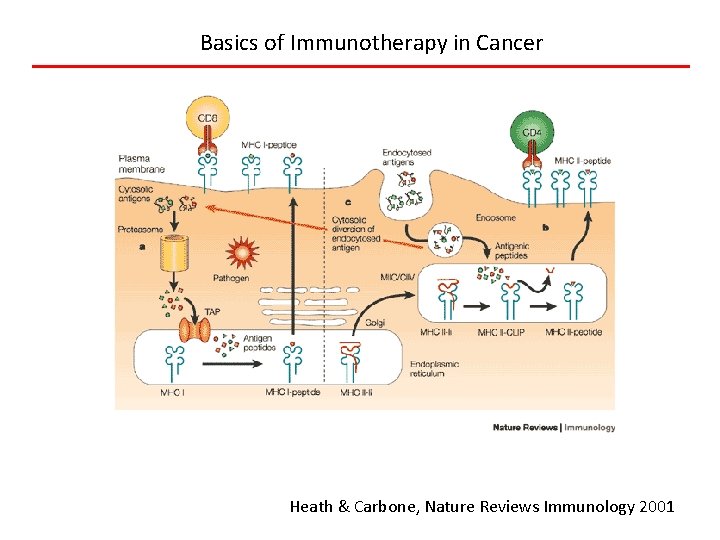

Basics of Immunotherapy in Cancer Heath & Carbone, Nature Reviews Immunology 2001

Neo-antigen Hypothesis • Neo-antigens are mutant proteins in cancer (10 s to 1000 s per cell), and can be catalogued by DNA sequencing • Are seen as foreign proteins and cells expressing them are attacked, except…. • Tumor cells have co-opted the normal tolerance mechanisms used to avoid autoimmunity (checkpoints) • Immunotherapy works because of tolerance blockers or neoantigen-specific T cells or vaccines Schumacher and Schreiber, Science 2015